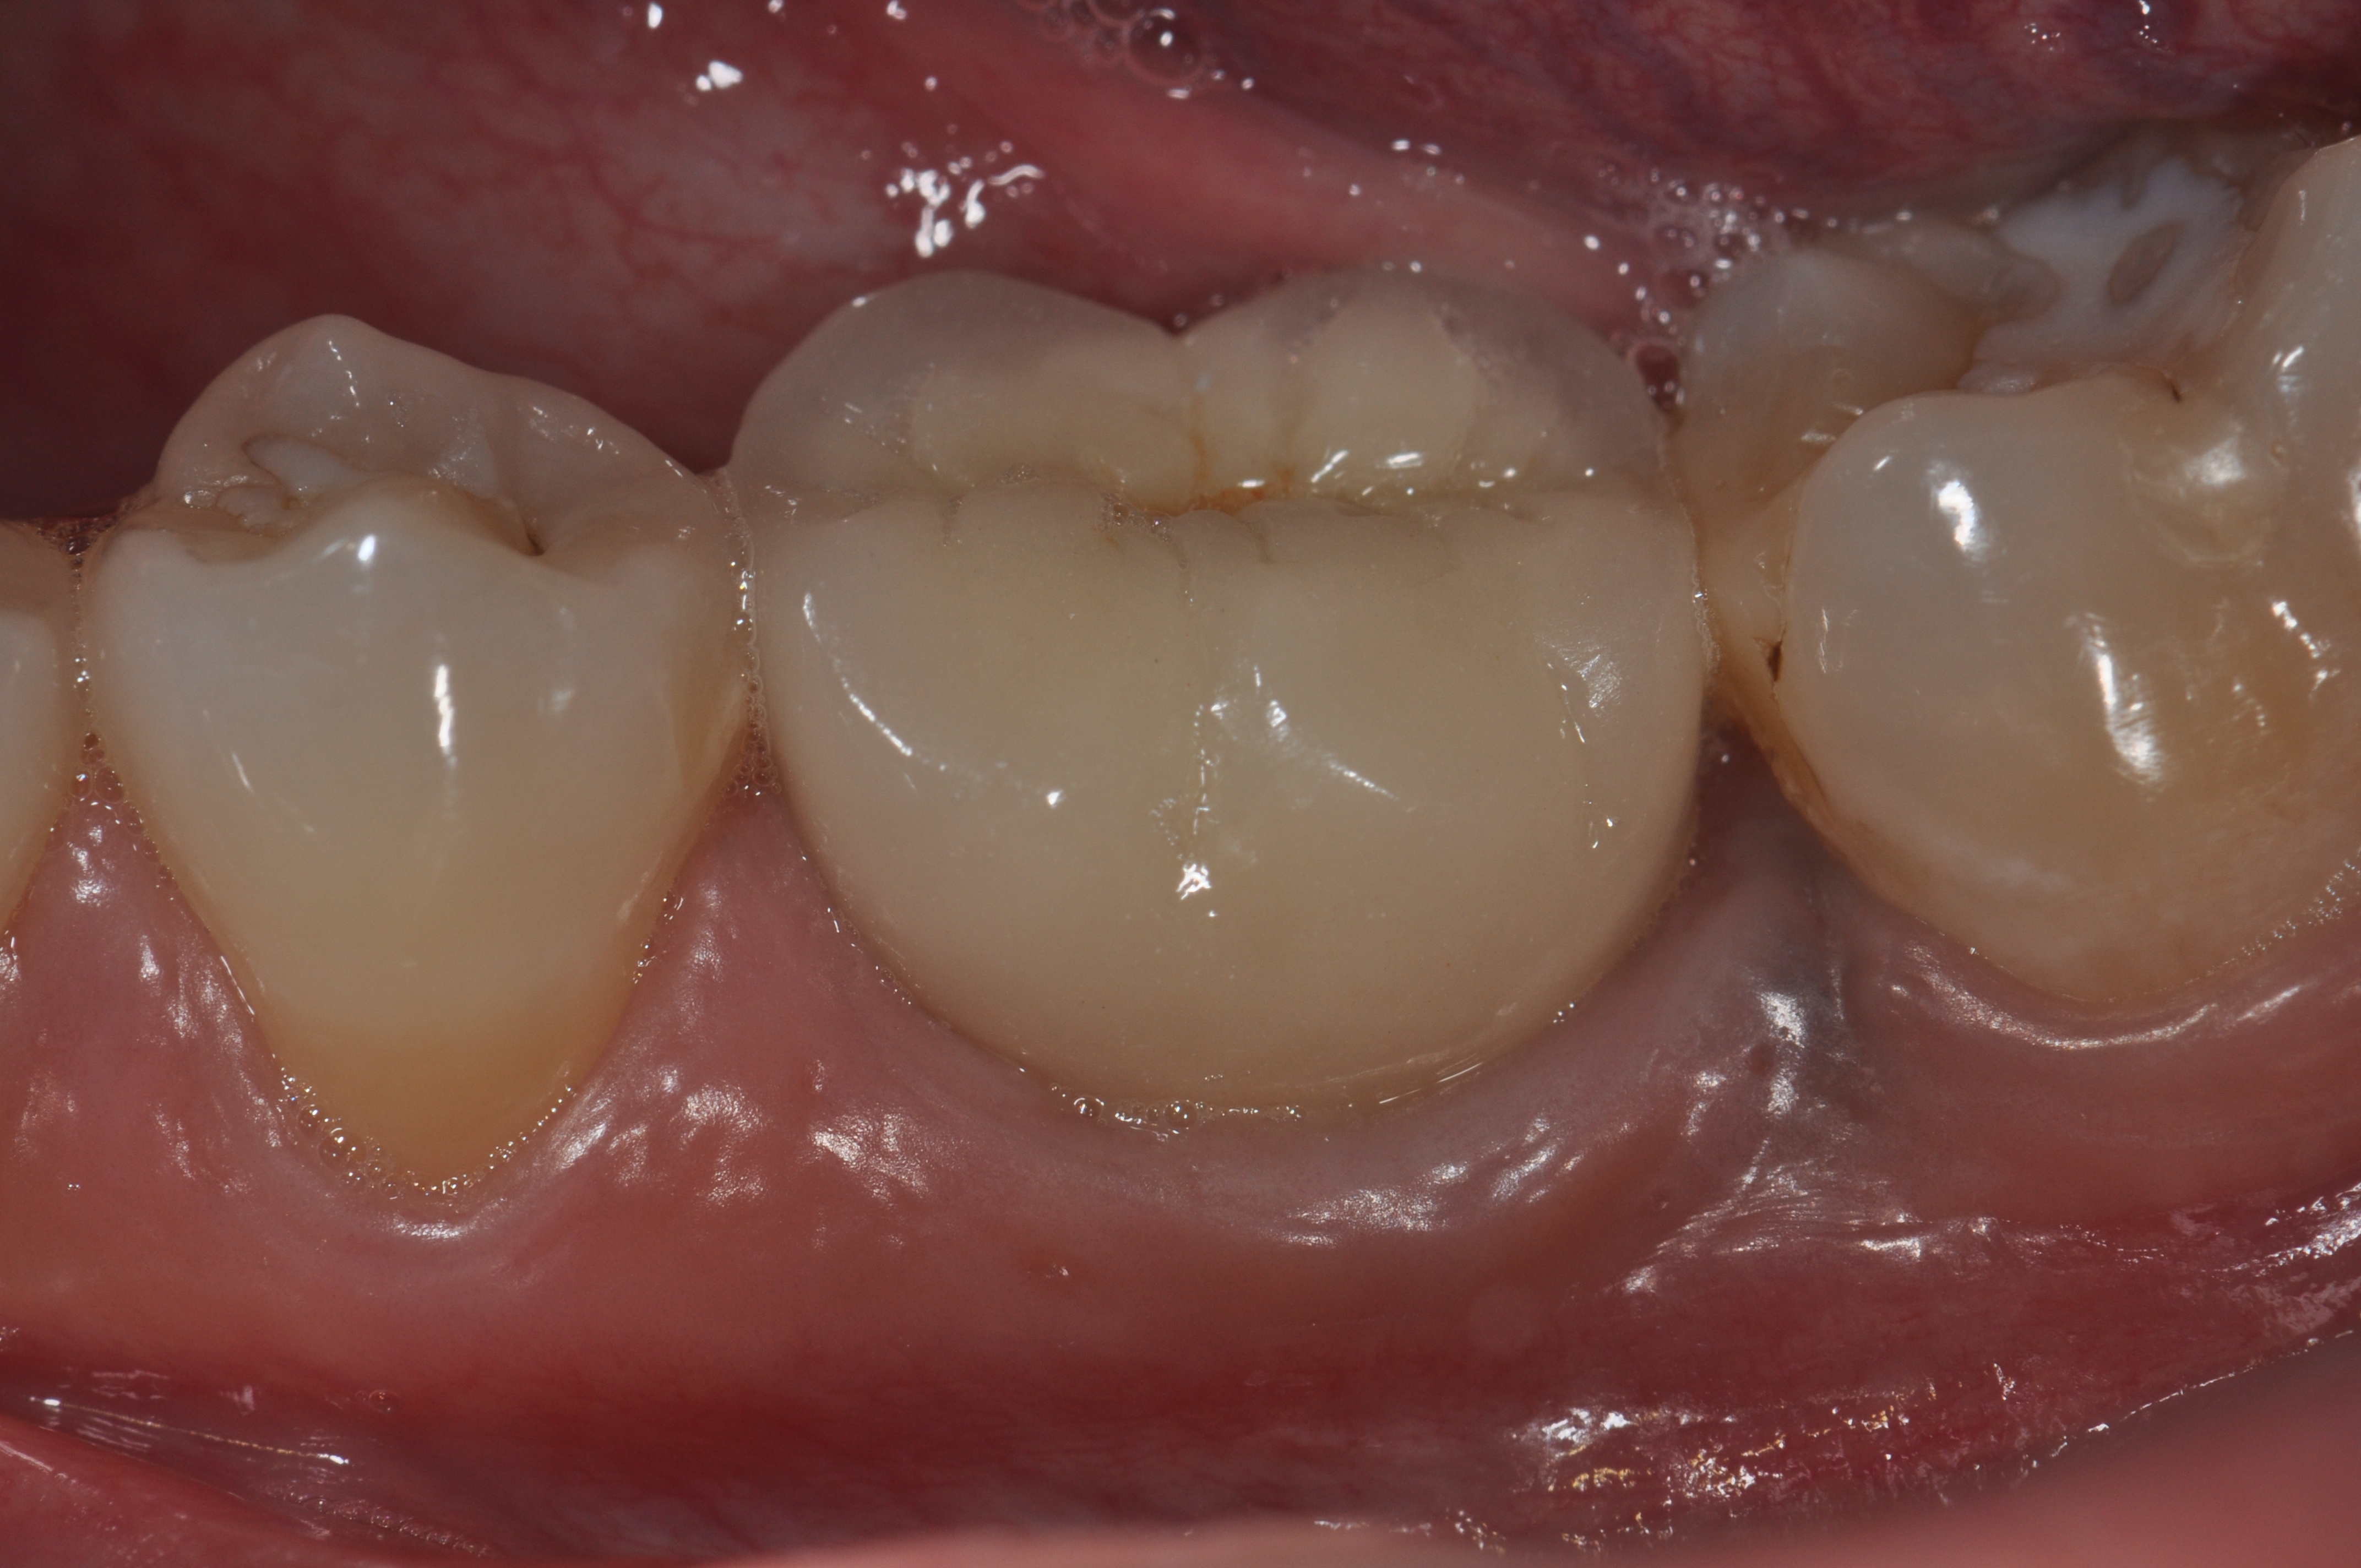

Fig 6. A clinical view of this area suggests that peri-implant mucositis is present. The tissue is swollen, it bleeds on probing, has 5 mm of probing depth, and exhibits purulent exudate.

Figure 6

Fig 7. Eight weeks after nonsurgical treatment that involved scaling of the area, which removed cement, and irrigation with an anti-inflammatory hydrogel, the area is healthy. No BOP is present, purulence is absent, and probing depths have been reduced to 4 mm as a result of the reduction in inflammation.

Figure 7